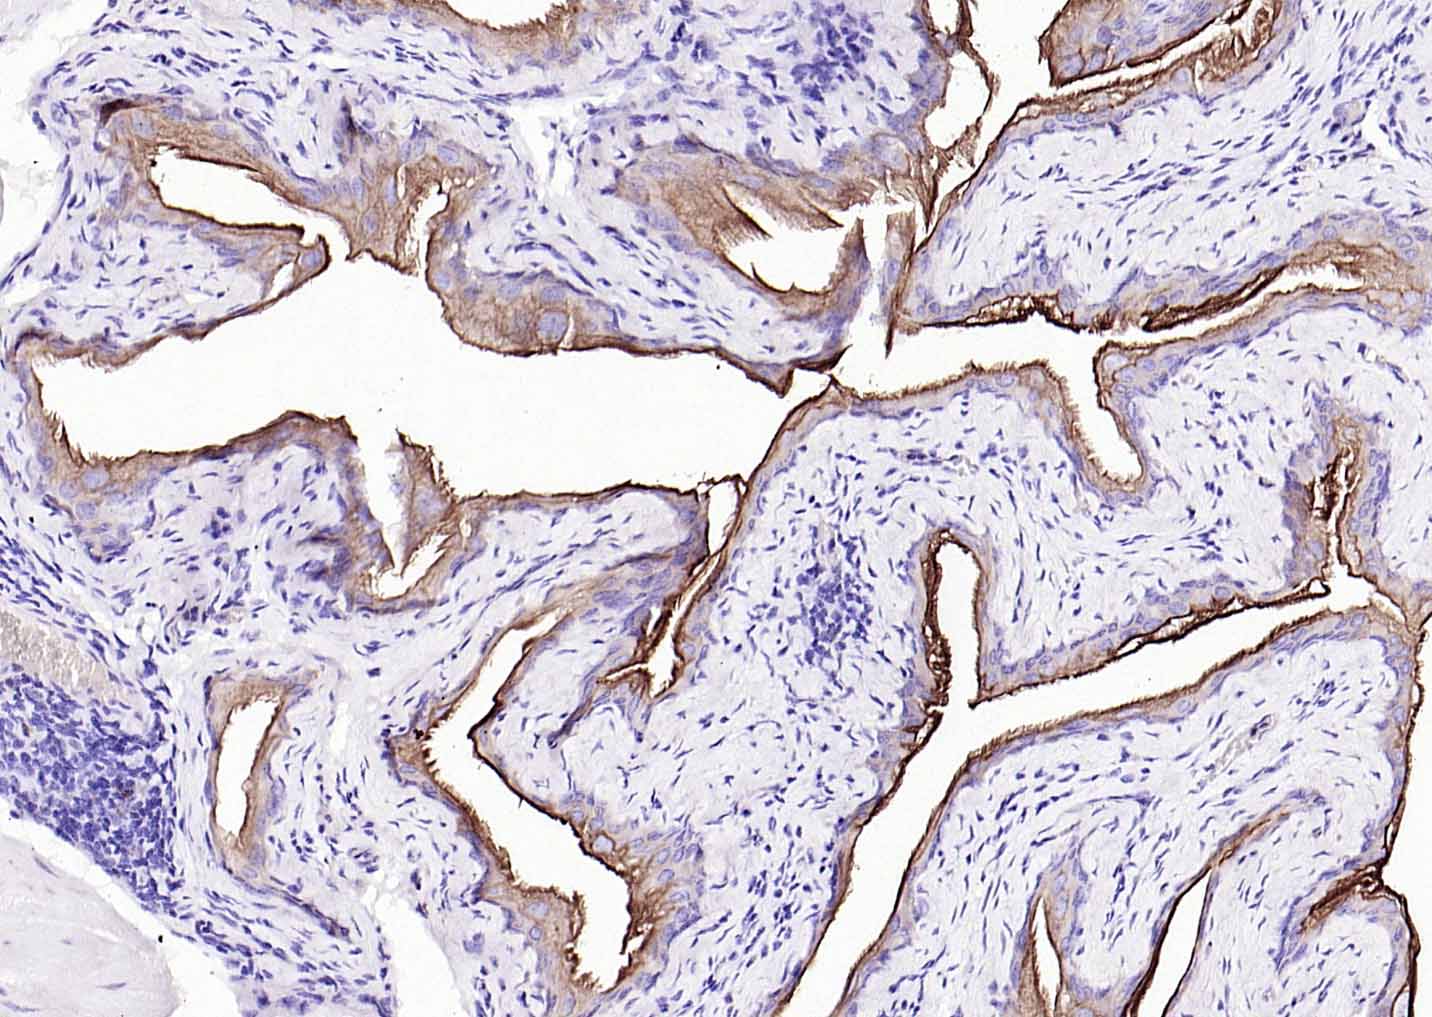

Vimentin is a developmentally regulated intermediate filament protein (IFP) found in cells of mesenchymal origin. It is believed to be involved with the intracellular transport of proteins between the nucleus and plasma membrane. Unlike other IFP proteins, vimentin is expressed, along with desmin, during the early stages of cellular development. During the development process, vimentin is exchanged for new, tissue-specific IFPs. Vimentin has been implicated to be involved in the rate of steroid synthesis via its role as a storage network for steroidogenic cholesterol containing lipid droplets. Vimentin phosphorylation by a protein kinase causes the breakdown of intermediate filaments and activation of an ATP and myosin light chain dependent contractile event. This results in cytoskeletal changes that facilitate the interaction of the lipid droplets within mitochondria, and subsequent transport of cholesterol to the organelles leading to an increase in steroid synthesis.

| IHC-P | Human, Mouse, Rat | 1:100-500 | |